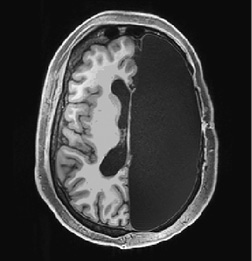

На протяжении нескольких часов хирург кропотливо удалял нежную розоватую мозговую ткань, составлявшую основу интеллекта Мэтью, его эмоций, способности говорить, чувства юмора, страхов и привязанностей. Извлеченная ткань, бесполезная в отрыве от своей биологической среды, отправлялась в маленькие контейнеры. Опустевшая половина черепа Мэтью медленно заполнялась спинномозговой жидкостью, что в ходе нейровизуализации отображалось черным пятном (рис. 1.1)2.

Рис. 1.1. У Мэтью хирургически удалена половина головного мозга

Источник: Kliemann D., et al. (2019). Intrinsic functional connectivity of the brain in adults with a single celebral hemisphere. Cell Reports. 2019 Nov 19; 29 (8): 2398–2407. © 2019, with permission from Elsevier